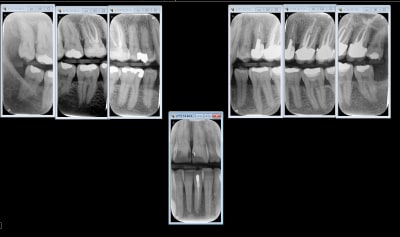

Capteur filaire, y a pas photo.

Une vidéo promo de chez carestream

Attention c'est un taille 2 ne va pas dans toutes les bouches et un Taille 1 les radios c'est en vertical.

Capteur RVG (filaire) sans hésitation. Moins cher, gain de temps, meilleure qualité d'image et meilleure ergonomie avec les angulateurs Xcp-Ora.

Tiens status meilleur rapport qualité - prix capteur taille 2 isensor woodpecker 1500 balles camera MD960 150 balles. Qui dit mieux ?

sinon avec le film chez les jeunes tu peux faire ca, pour le depistage des caries: